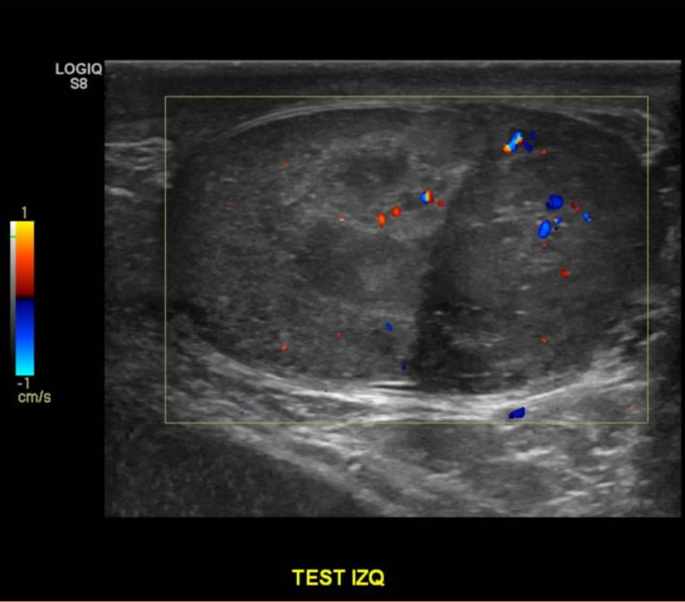

Descripción de hallazgos:

Testículo izquierdo heterogéneo, con áreas hipoecogénicas, tenue señal al Doppler, con imagen nodular hipoecogénica, heterogénea, con señal al Doppler, sugerente de neoplasia

Hallazgos: Testiculo derecho de tamaño, forma y estructura normal. Parénquima homogéneo sin lesiones nodulares El testículo izquierdo se observa aumentado de tamaño. Presenta alteración de la estructura de todo el parénquima con múltiples imágenes nodulares hipoecogénicas vascularizadas que miden hasta 2 cm de diámetro En la cabeza del epididimo derecho se observa un quiste de 2,2 mm de diámetro. Epididimo izquierdo sin alteraciones No se observa hidrocele No se observa dilatación de los plexos pampiniformes.

Impresión Diagnóstica: Obs neoplasia testicular izquierda multifocal. Quiste epididimario derecho